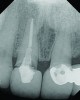

Fig 2. Periapical radiograph revealing the fractured central incisor.

Figure 2

A 63-year-old female patient presented with mobility of her right maxillary incisor, tooth No. 8, secondary to endodontic therapy (Figure 1). Her medical and dental histories were non-contributory. Clinical and radiographic evaluations revealed an 8-mm probing depth on the palatal aspect. The tooth was deemed to be fractured (Figure 2). The treatment plan accepted by the patient was for extraction, immediate implant placement, and immediate provisional restoration, if possible.